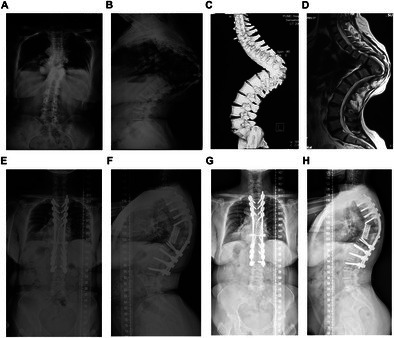

目的:严重的脊柱畸形,包括脊柱侧凸和脊柱后凸,由于神经系统并发症的风险增加,在矫正手术中提出了重大挑战。术前危险因素的识别对于优化预后和预防并发症至关重要。方法:回顾性队列研究分析了2002年1月至2022年5月接受手术治疗的130例严重脊柱畸形患者。全面收集和分析术前临床、影像学和手术资料,目的是确定神经系统并发症的危险因素。进行单因素和多因素logistic回归分析以确定独立预测因素。结果:共纳入患者130例,女性比例50%,平均年龄21.4±15.3岁,其中18例(13.8%)出现术后神经系统并发症。术前脊髓异常(并发症组为38.9%,非并发症组为8.9%,p = 0.001)和较高的后凸角度(并发症组为112.4°,非并发症组为98.2°,p = 0.018)是显著因素。并发症组术中神经监测报警发生率明显高于并发症组(38.9% vs. 15.9%, p = 0.022)。两组手术时间(p = 0.095)和出血量(p = 0.179)差异无统计学意义。较高的后凸角度(OR = 1.027, 95% CI: 1.001-1.055, p = 0.045)和脊髓异常的发生(OR = 6.715, 95% CI: 1.694-26.615, p = 0.007)是手术神经系统并发症的独立预测因素。结论:术前脊髓异常和较高的后凸角度是术后神经系统并发症的独立危险因素。全面的术前评估对于优化这些高危患者的手术策略至关重要。

Results: A total of 130 patients were included in the study, with a female ratio of 50% and a mean age of 21.4 ± 15.3 years, and 18 (13.8%) of them experienced postoperative neurological complications. Significant factors included preoperative spinal cord anomalies (38.9% in the complication group vs. 8.9% in the non-complication group, p = 0.001) and a higher kyphosis angle (112.4° in the complication group vs. 98.2° in the non-complication group, p = 0.018). The incidence of intraoperative neuromonitoring alarms was significantly higher in the complication group (38.9% vs. 15.9%, p = 0.022). No significant differences were observed in operative time (p = 0.095) or blood loss (p = 0.179). A higher angle of kyphosis (OR = 1.027, 95% CI: 1.001-1.055, p = 0.045) and the occurrence of spinal cord anomalies (OR = 6.715, 95% CI: 1.694-26.615, p = 0.007) were independent predictors of surgical neurological complications.

Conclusions: Preoperative spinal cord anomalies and a higher kyphosis angle are independent risk factors for postoperative neurological complications. A comprehensive preoperative evaluation is essential for optimizing surgical strategies in these high-risk patients.